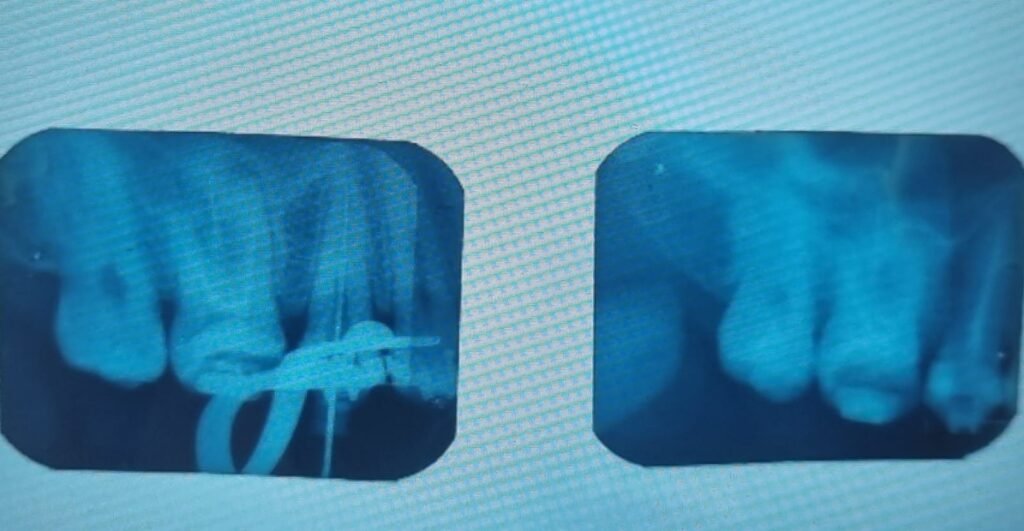

Endodoncia

Si presentas infección dental, ya sea por caries o por alguna fractura en tu diente, probablemente el paso a seguir es el tratamiento del nervio de tu diente. Con este procedimiento podemos preservar tu diente. Acude con nosotros para un diagnóstico correcto y así poder determinar si este tratamiento es una opción para ti.